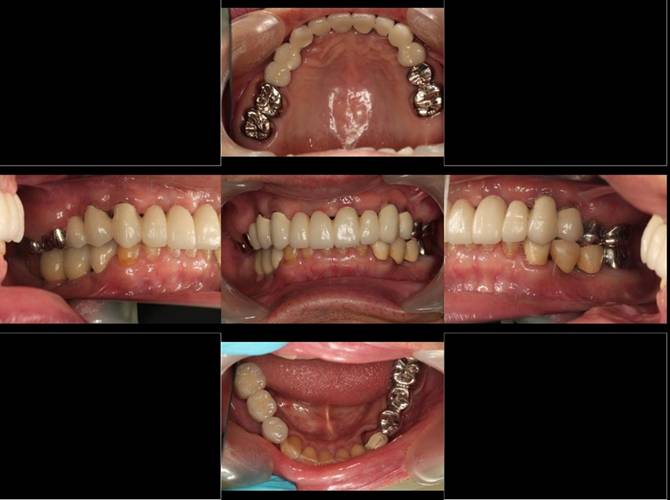

術後。上部構造はハイブリッドレジンです。しっかり嚙めるようになり喜んでいただきました。

上顎

下顎

上部構造装着後6年。ハイブリッドレジンを使用したため、少し艶がなくなってきました。上部構造の材料には金属、ハイブリッドレジン、セラミックなどがあります。セラミックはきれいですが欠けやすいため、最近はフルジルコニアを使っています。

上顎 少しすり減ってきました。

下顎。12か月に一度メインテナンスをしています。

インプラント装着後6年。順調に経過しています。12か月毎のメインテナンスをしています。